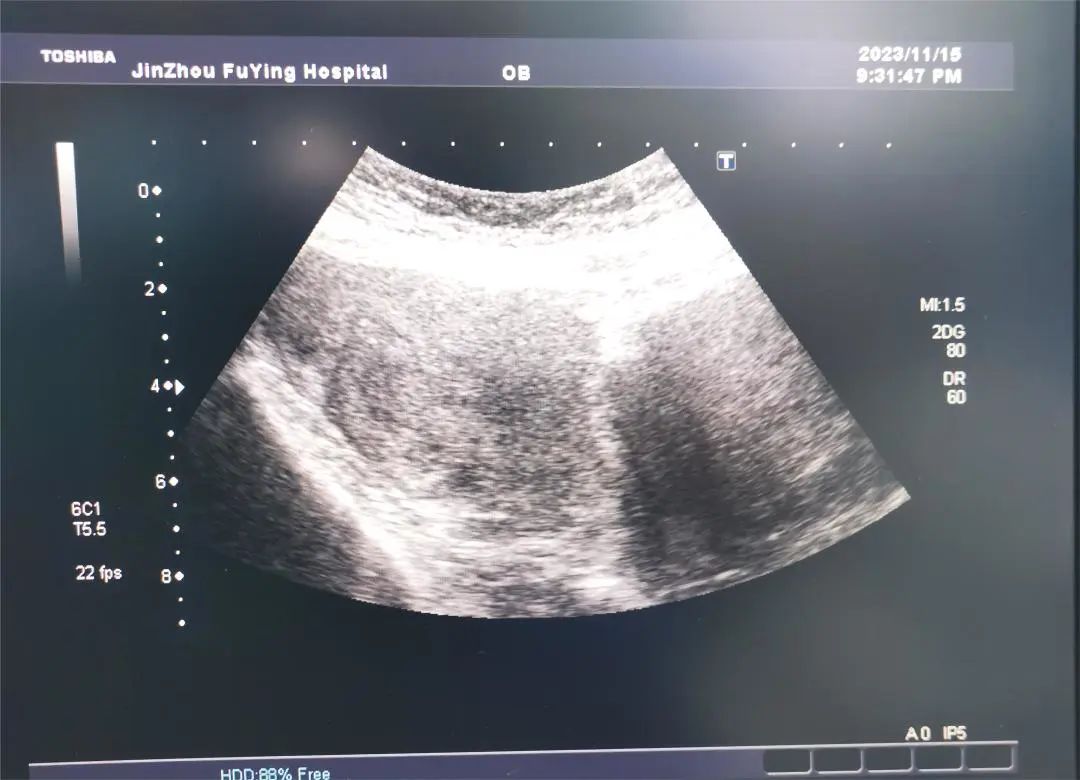

门诊医生详细询问患者病史,“患者妊娠8周”,内诊宫颈前壁可触及约7.0×5.0cm肿物,宫颈被压迫变形,评估手术难度大,引起我科高度重视;人流手术室金医生在看到病志后,再次对患者病情进行评估,巨大子宫颈肌瘤压迫宫颈导致宫颈管变形、狭窄可能带来的一系列风险,如进入宫腔困难等,在术前请超声科会诊并对术中可能发生的情况进行讨论后,向患者及家属详细交代病情、讲解手术的难度及风险。经过医生与患者及家属的反复交代沟通后,在患者及家属的信任与期待中,手术平稳有序的开始了……

在麻醉、超声、手术医生的默契配合下,手术顺利完成。